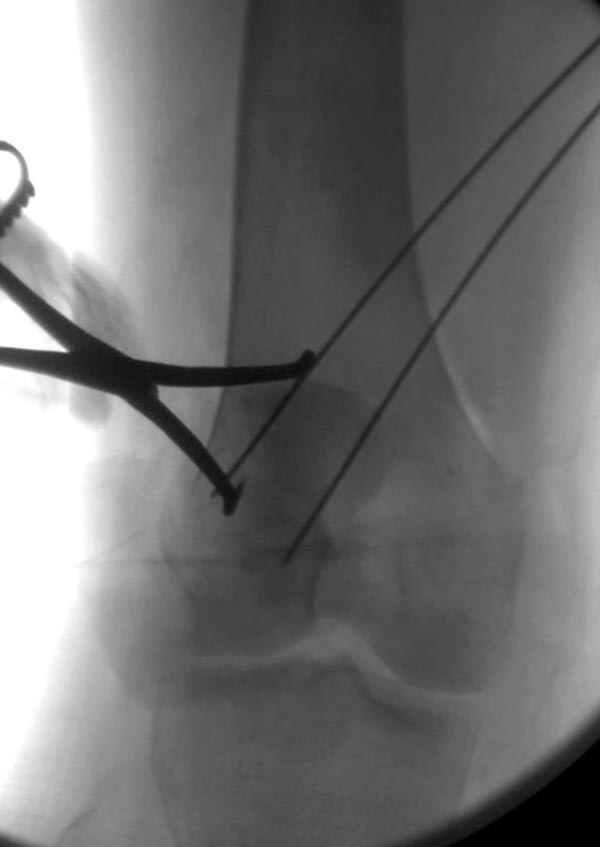

Сегодня досылаю остальные снимки, которые не прошли вчера. Как вчера писал, после фиксации перелома надколенника с дефектом кости и собственной связки, наложили ваккуум и наружный фиксатор. (снимки 4-9)

Внешний фиксатор держим около 6 недель, поэтому был выбран метод фиксации шурупами и еще линия перелома была диагональной, не было нужды в tension band technique, cannulated screws удобнее, провел спицы и по ним шурупы.

Связка ушита обычными сухожильными швами конец в конец, не было нужды проведения шва через надколенник, из-за ех-фиксатора.

Внешний фиксатор снимаем за пару недель до пластики крестообразных связок, мой партнер специалист по спортивной травме, считает оптимально в 6-8 недель, только не могу догадаться, чем будет производить пластику поврежденной собственной связки?